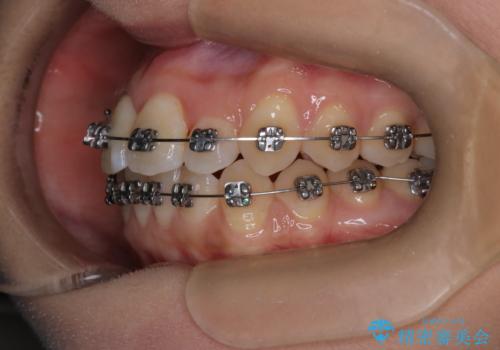

- メタル装置

- 前歯のがたつきを治したいという主訴で来院されました。1年後に転勤の可能性があり短期間での治療を希望されました。今回は非抜歯の治療を計画し、IPRと拡大をし、前歯の叢生を改善しました。

前歯のがたつきを治しながら2番の反対咬合も改善させました。短期間で終了し満足していただけました。